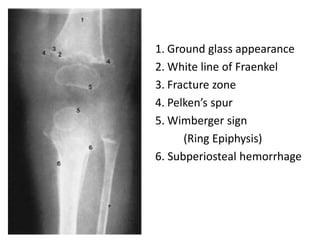

1. Ground glass appearance

2. White line of Fraenkel

3. Fracture zone

4. Pelken’s spur

5. Wimberger sign

(Ring Epiphysis)

6. Subperiosteal hemorrhage

Diagnosis

Radiological findings

1. Ground glassappearance 2. White line of Fraenkel 3. Fracture zone 4. Pelken’s spur 5. Wimberger sign (Ring Epiphysis) 6. Subperiosteal hemorrhage

Diagnosis  Clinical picture Radiologicalfindings  Laboratory tests less satisfactory 1. Plasma vitamin C level < 0.6 mg/dl 2. Ascorbic acid level in serum white cells or buffy layer of centrifuged blood < 0.1 mg%. 3. Excretion of ascorbic acid in urine < 1.5 mg after a loading dose of 20 mg/kg IV 4 hours earlier. 4. No or < 20% excretion of ascorbic acid in urine 24 hrs after a loading oral dose of Vitamin C 10 mg/kg.